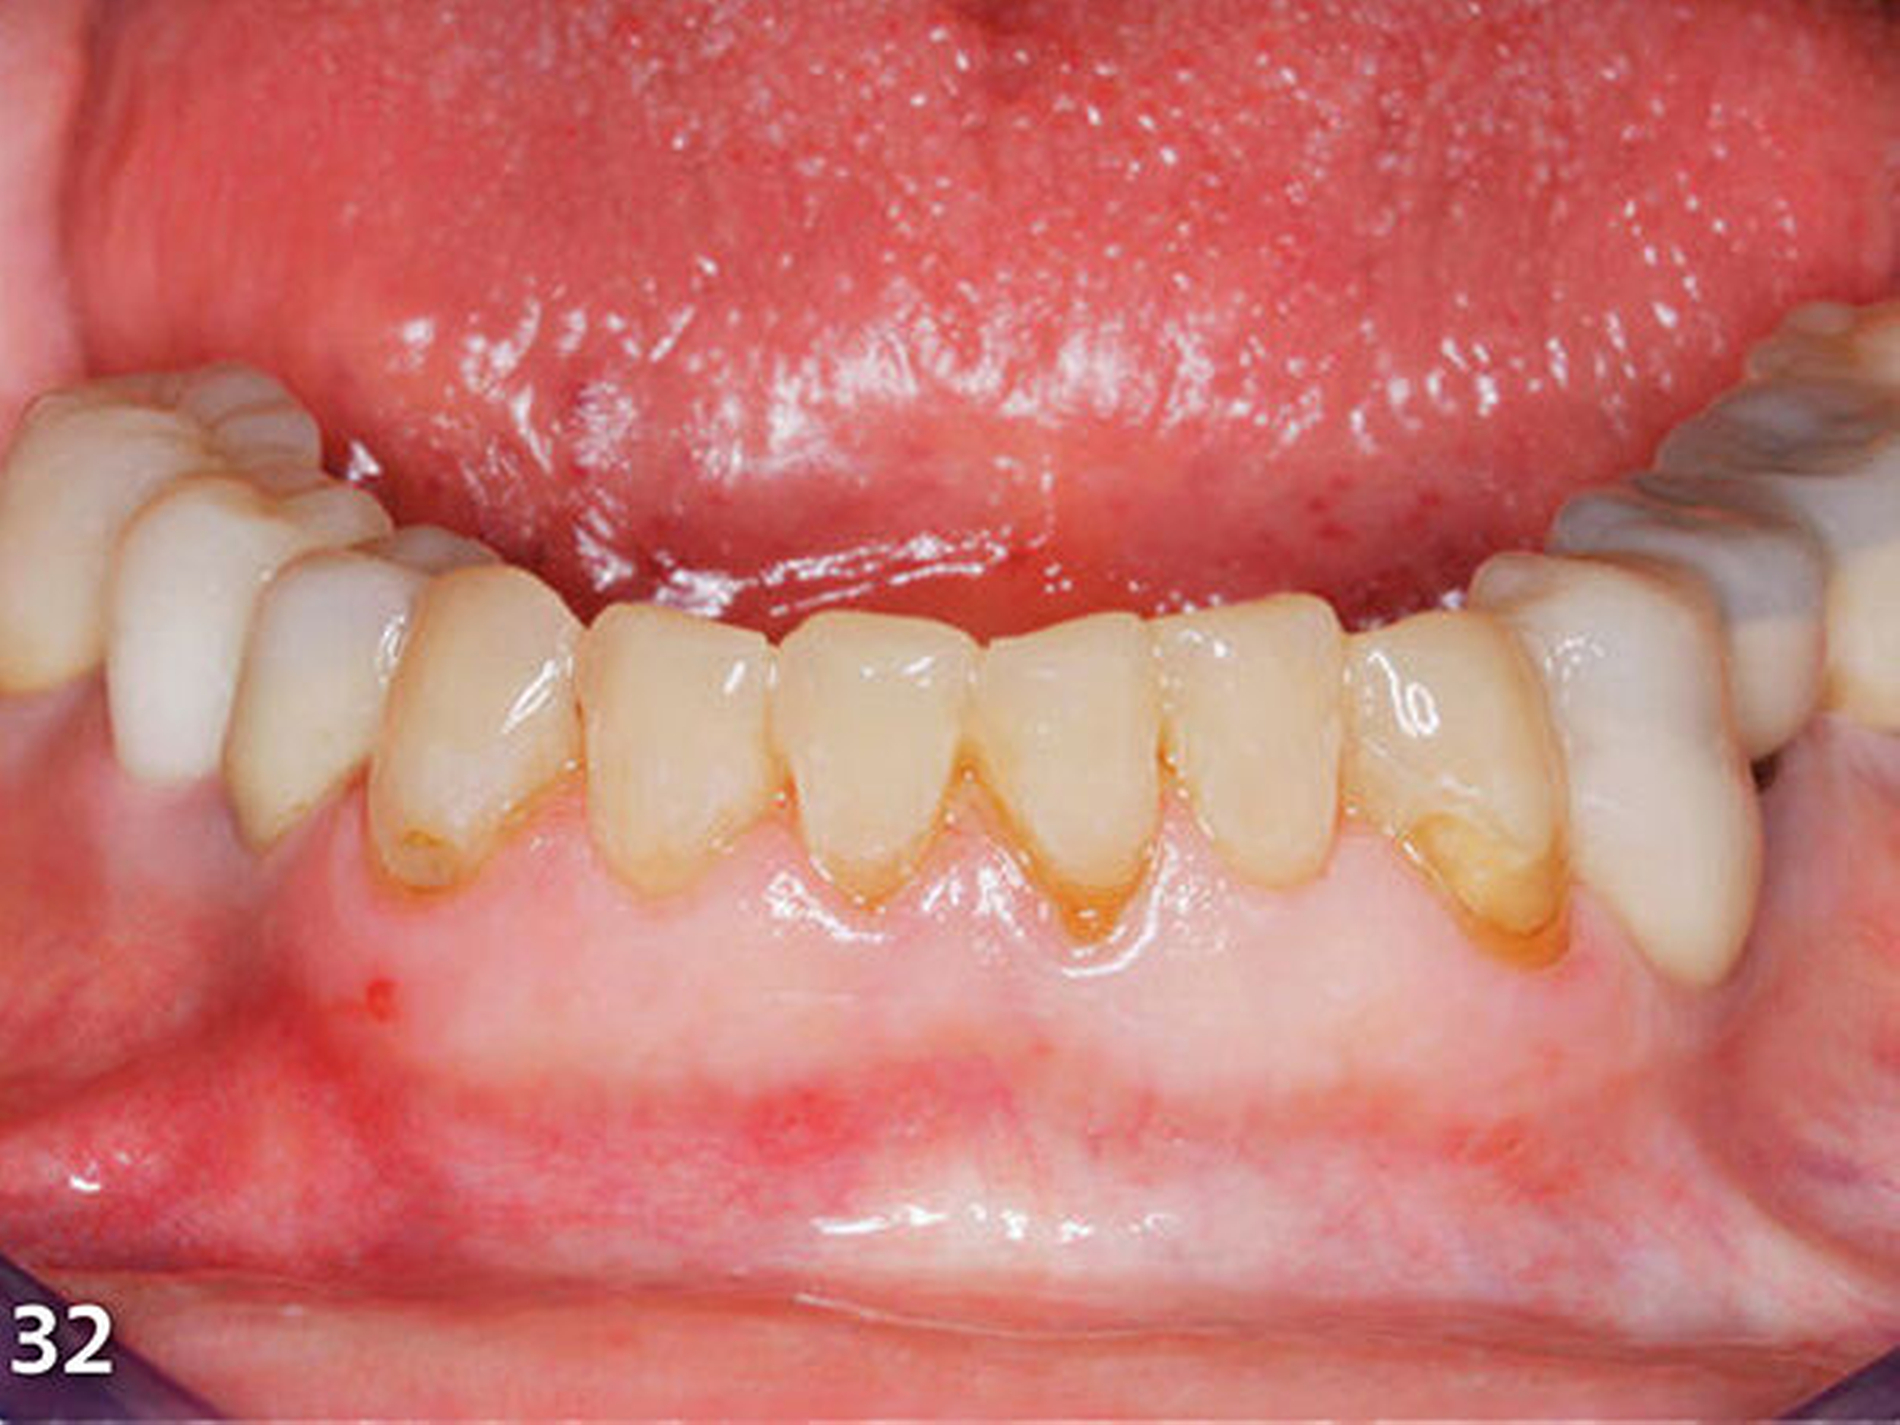

Nach dem Ausarbeiten und Polieren sämtlicher Restaurationen (Abb.31 und 32) wurden die statische und die dynamische Okklusion nochmals kontrolliert; es zeigte sich eine gute Übereinstimmung mit dem okklusalen Kontaktmuster aus dem Wax-up (Abb.33). Da sämtliche Restaurationen ohne Verabreichung von Lokalanästhesie aufgebaut wurden, konnte die Patientin sofort nach Abschluss der Behandlung, nach einer kurzen Phase der Lockerung der Kaumuskulatur, ein erstes positives Feedback zur neuen Unterkieferposition geben (Abb.34 und 35).